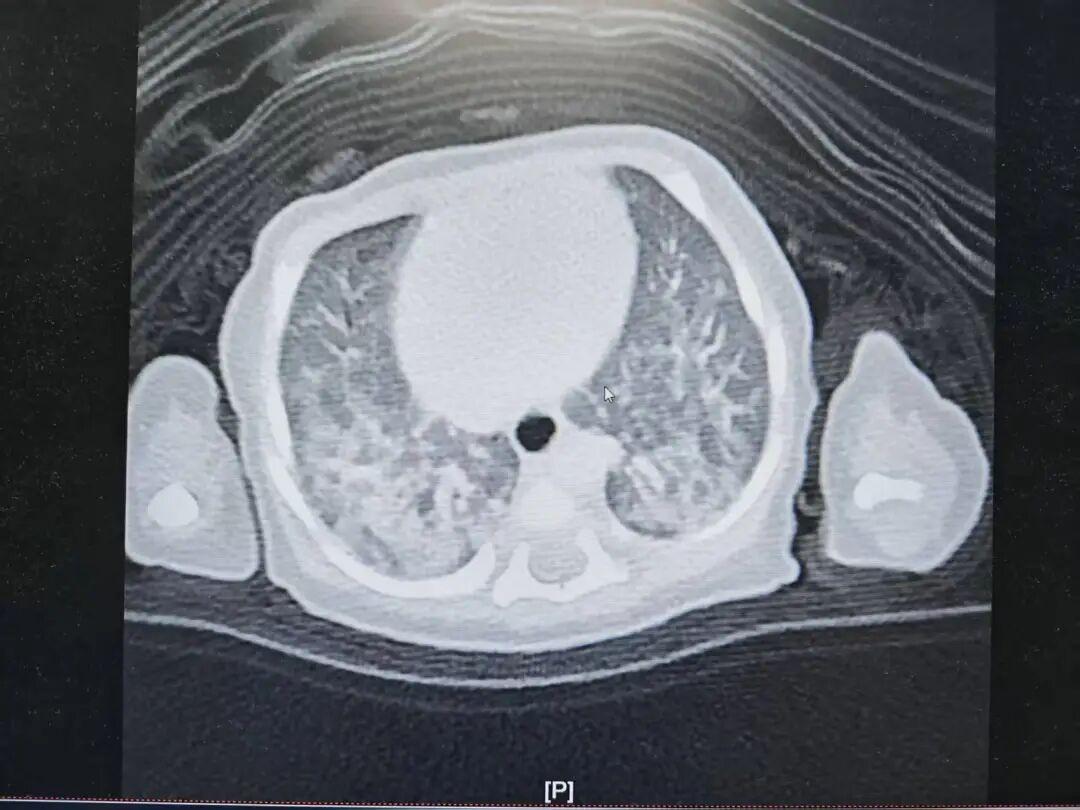

面对宝宝持续离不开氧气的困境,NICU及时完善CT检查,两例患儿均提示肺内多发斑片影,考虑胎粪吸入的沉积及炎性渗出,果断联系支气管镜下肺泡灌洗。

儿童呼吸内科团队在麻醉手术中心的保驾护航下,将一根纤细柔软的内镜经鼻腔轻柔地送入新生儿气道。屏幕上清晰地显示出气道内黏附的胎粪栓子。团队随即进行肺泡灌洗,用时不到20分钟,便将堵塞物清理干净。术后,两名患儿呼吸状况改善,均成功脱离了氧气支持。